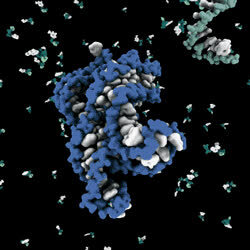

每时每刻,你的身体中正进行着一场大战.这场起源于几十亿年前的战斗现今仍然在我们每个的体内发生.这是关于病毒入侵的故事——细胞的生死之战.这部影片从细胞的内部世界揭示了人体细胞系统的精细机制:从狂热的扮演着针对进出细胞的每个物体的安全防御系统的细胞膜,贯穿细胞的输送物质颗粒的细胞架,以及保持整个细胞世界运转的线粒体,到保存着DNA的细胞核和成千上万种各自拥有不同的蛋白质的合成。而病毒正是旨在劫持这套系统以为其所用——制造更多的病毒。

正如科幻小说中描述的一样,这是一个关于人类细胞与腺病毒争夺我们DNA控制权并持续了数亿年的战争故事。取材于对细胞的最新发现,这部惊心动魄的纪录片第一次将我们带入人类细胞绚丽的内部世界。在细胞可视化的世界级专家、分子生物学家和好莱坞电脑三维动画设计师的帮助下,观众将在最新发现的、宛如外星世界的细胞内部体验一次惊悚和科学的电影旅程。这部影片为最前沿的生物学加入了史诗般的故事情节,向我们揭示了一个从未有人涉足的世界。

3. 每个细胞含有23对染色体,这些染色体是由超过3000000000个碱基对的,含有20000个基因。我们就此开始细胞内的“星际”旅行吧。

4.线粒体,看上去像细菌,是细胞内微小的细胞器,它是活细胞里微小的发电机,以ATP的形式生产我们几乎所有的能量,它就如同星际探险的飞船一般。

5.RNA聚合酶:催化以DNA为模板、三磷酸核糖核苷为底物、通过磷酸二酯键而聚合的合成RNA的酶。其行为奇怪,在产生RNA转录本时停停顿顿,经常休息。

6.核苷酸各就各位,排列聚合。

7.驱动蛋白:展现“行走”的力量。它能利用ATP水解所释放的能量驱动自身及所携带的货物分子沿微管运动的一类马达蛋白,与细胞内物质运输有关。

8.RNA复制就是以DNA为模板合成RNA。如果说DNA对蛋白质来说是一张图纸,那么RNA就是能够下达指令的建筑商。